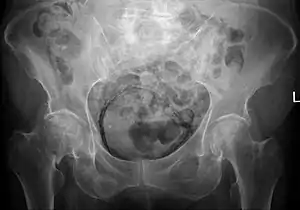

Emphysematous cystitis